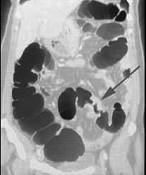

男,55岁,左下腹胀痛、并可触及包块,结合图像,应诊断为()A.结肠Crohn病B.结肠癌C.结肠腺瘤D.肠结核E.慢性溃疡性结肠炎

问题 男,55岁,左下腹胀痛、并可触及包块,结合图像,应诊断为()

选项 A.结肠Crohn病 B.结肠癌 C.结肠腺瘤 D.肠结核 E.慢性溃疡性结肠炎

答案 B